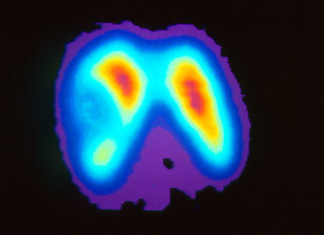

Buenas noticias: las migrañas afectan la cabeza, pero no el cerebro

Las migrañas afectan actualmente a un 20 por ciento de la población femenina, y mientras que estos dolores de cabeza son comunes, hay muchas...